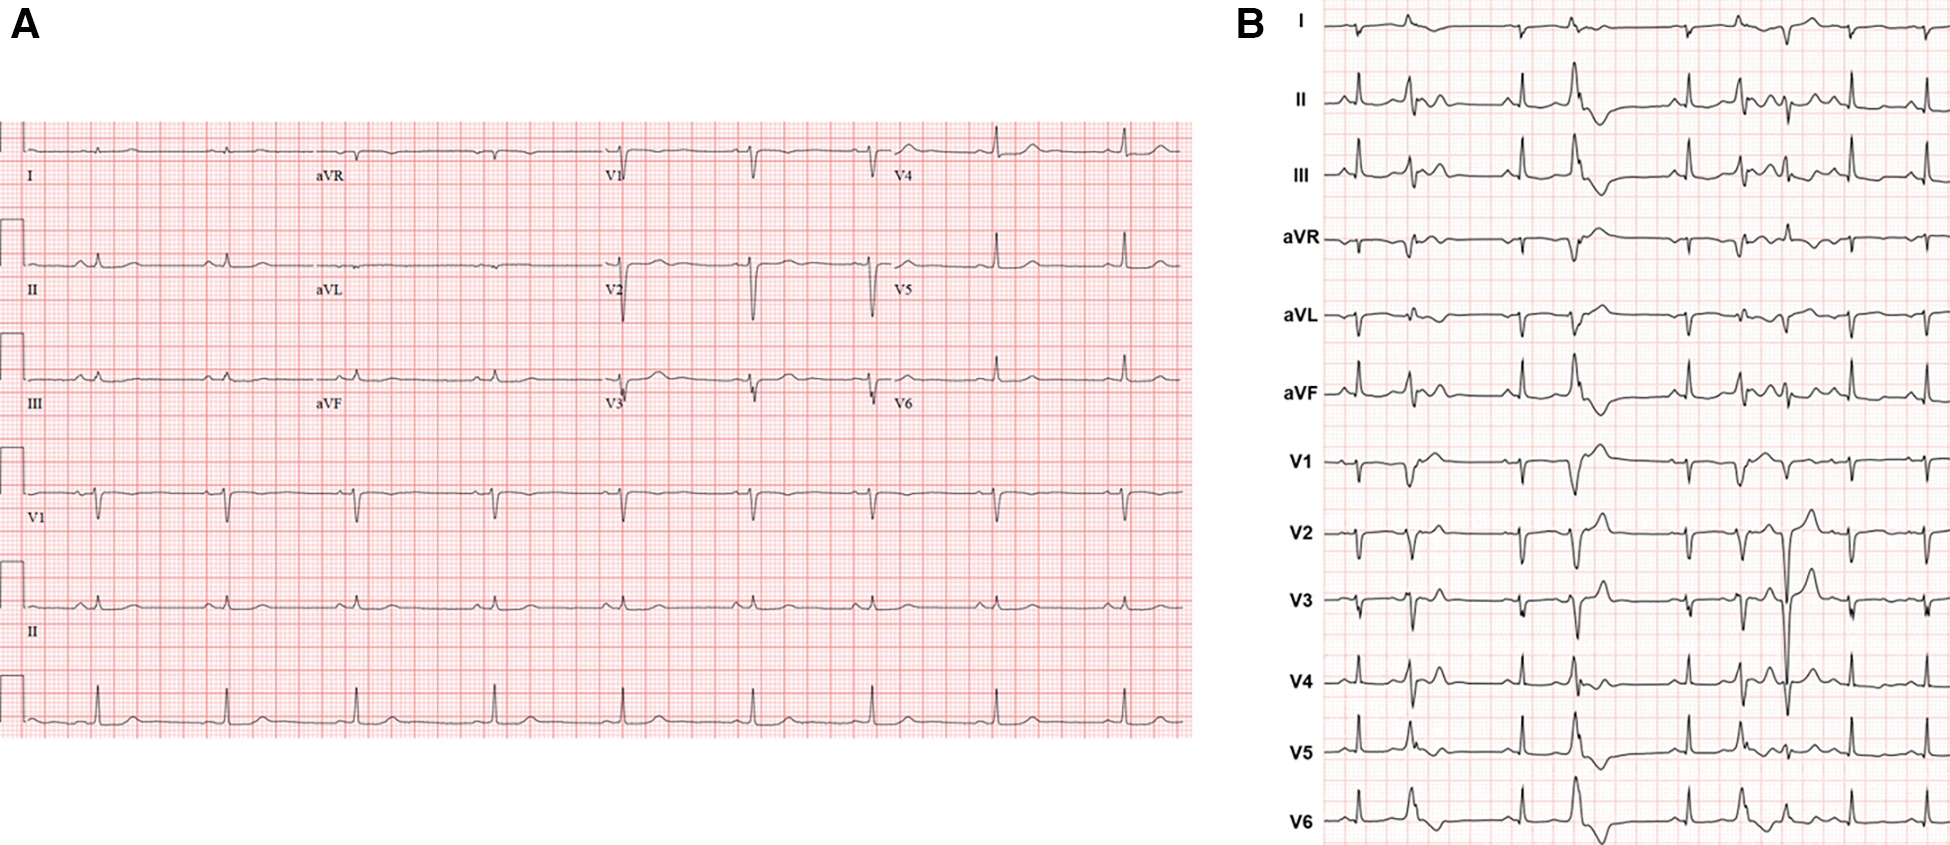

A 41-year-old female with no significant past medical history and no family history of cardiomyopathy or sudden cardiac death was referred for evaluation of persistent frequent premature ventricular contractions (PVCs) following a catheter ablation performed at an outside institution. She was in her usual state of health until a year prior to evaluation, when she developed palpitations, dyspnea on exertion, chest pain, and pre-syncope. The initial evaluation at our institution revealed diffuse low voltage QRS complexes on the 12-lead electrocardiogram, but no inverted T waves or epsilon waves (Figure 1A). A 12-lead Holter monitor showed 28% burden (25,000/24 h) of PVCs with more than 5 different morphologies consistent with RV inflow and outflow tract (RVOT) exits (Figure 1B). A transthoracic echocardiogram revealed normal LV and RV ejection fraction, and normal biventricular dimensions. Cardiac magnetic resonance (CMR) imaging revealed a borderline increased RV chamber size (RV end-diastolic volume indexed for body surface area 107 ml/m2, normal range 51–103 ml/m2) with normal systolic function (RVEF 51%, LVEF 58%) without dyssynchrony, akinesia, or dyskinesia, and no findings suggestive of RV or LV fibrosis, myocarditis, infarction, or late gadolinium enhancement (Figure 2). There were no pertinent findings on physical examination with the exception of occasionally irregular heart sounds due to PVCs.

Figure 1

(A) Representative 12-lead electrocardiogram. (B) Twelve-lead Holter monitor tracing. Holter showed more than 5 different RV inflow and outflow tract PVC morphologies with a total burden of 28% over 24 h. Follow-up 24-h Holter 3 months post-ablation demonstrated 6% PVC burden.